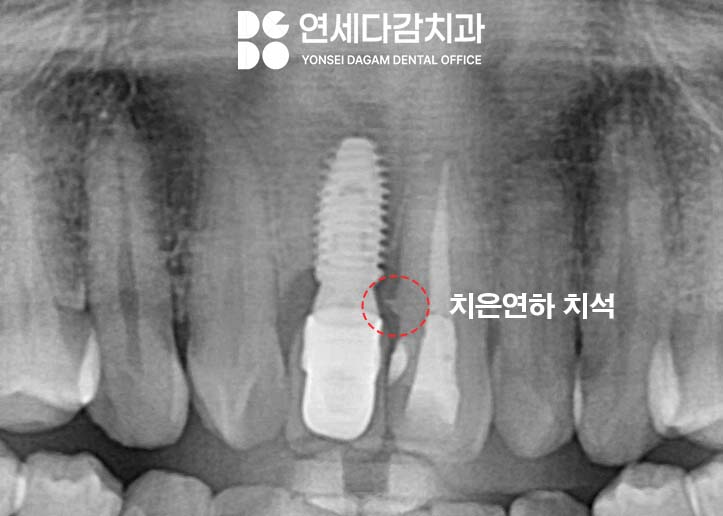

또한 엑스레이를 통해 치아 내부도

면밀히 검진하여,

치은연하 치석같은 잇몸질환을

유발하는 원인들은 없는지

확인하는 것도 중요한 고려사항입니다.

이후 잇몸 치료를 통해

치은 연하 치석을 깨끗하게 청소합니다.